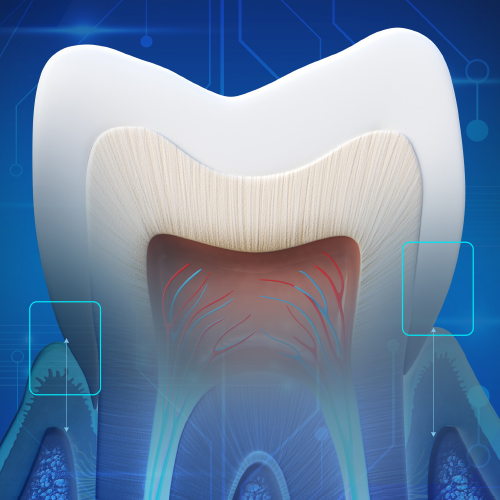

New Directions in Endodontics

Tuesday, April 2, 2024

This Compendium eBook features a continuing education (CE) article on the management of endodontic flare-ups. This eBook also includes an article on intentional replantation as a predictable and cost-effective option for preserving a natural tooth and as a favorable alternative to conventio...

Endodontic Updates

Wednesday, March 22, 2023

This Compendium eBook offers a continuing education (CE) article on unseparated fractures and their diagnostic complexities. This eBook also includes a case report article on the use of cone-beam computed tomography for the analysis of atypical root canal anatomy. Download to earn 2 FREE CE...

Endodontic Advances

Friday, October 21, 2022

This Compendium eBook offers a continuing education (CE) article that examines the most recent guidelines of the American Association of Endodontists and the American Dental Association regarding the prescription of antibiotics, and outlines the best choices for antibiotic treatment for bot...

Breakthroughs in Dental Pain Management

Friday, November 12, 2021

This Compendium eBook offers a continuing education (CE) article that explores the various theories for the etiology of dentin hypersensitivity, and discusses a variety of noninvasive treatments, as well as some of the more aggressive alternatives that may be needed for patients with sever...

Developments in Endodontics

Wednesday, July 14, 2021

This Compendium eBook offers a continuing education (CE) article on mineral trioxide aggregate (MTA) and its composition, clinical applications, and research findings. This eBook also includes a case report on the use of conebeam computed tomography (CBCT) to diagnose anatomical disparities...

Developments in Dental Pain Management

Monday, May 17, 2021

This Compendium eBook features a continuing education (CE) article that discusses how “Frontline Temporomandibular Joint/Orofacial Pain Therapy for Every Dental Practice” is a critical topic as patients with chronic orofacial pain will often turn to their dentists first. The accompanyin...

Advancements in Endodontics

Monday, August 31, 2020

This Compendium eBook consists of a continuing education (CE) article on ridge preservation strategies in children who experience anterior tooth trauma. A second article is a case report that uses cone-beam computed tomography (CBCT) for diagnosis, evaluation, and endodontic management of a...

Innovations in Endodontics

Friday, May 8, 2020

This Compendium eBook offers a continuing education (CE) article that features the importance of proper pretreatment diagnosis and the identification of etiology in endodontic retreatment. A second article provides an up-to-date report on comprehensive endodontic pain management.

Innovative Technologies Within Endodontic Practices to Improve Treatment Outcomes: The Importance of Patient Referral

Wednesday, November 20, 2019

This Compendium eBook features a continuing education (CE) article on advancements in technology that have provided a better understanding of the complex anatomies found in root canal systems.

Spotlight on Endodontics

Thursday, August 1, 2019

This Compendium eBook includes a CE article that describes techniques for placement of posts. The second article presents a case report on a multidisciplinary approach to the management of a mandibular first molar.

Today's Trends in Endodontics

Wednesday, February 6, 2019

The relationship between endodontics and restoration is explored in two continuing education (CE) articles presented in this special Compendium eBook. The first article explains the importance of obtaining a pulpal and periradicular diagnosis before restorative treatment. The second discuss...

Current Topics in Endodontics

Monday, September 24, 2018

This special Compendium eBook presents two articles on topics in endodontics. The first article, a continuing education course with a quiz for 2 credits, examines various steps of endodontic treatment and how, from a restorative standpoint, treatment can be improved for better long-term predictabili...

Advances in Endodontics

Wednesday, February 14, 2018

This eBook provides two continuing education articles on endodontics topics. The first article reviews solutions to the problem of endodontic rotary file breakage. In the second article, the authors examine mineral trioxide aggregate (MTA), a material that has become vital in endodontic dentistry.

Updates in Endodontics

Wednesday, December 6, 2017

This special Compendium eBook provides two CE articles to increase practitioners' knowledge of endodontics topics. The first article describes the vital role that irrigation plays in successful endodontic treatment. The second article addresses the complexity of the pulp root canal and the difficult...

Endodontics

Monday, April 17, 2017

This special Compendium eBook discusses how local anesthesia can be used to provide pain-free endodontic therapy. Also, a successful pulp capping procedure is described along with stepwise excavation associated with restorative treatment for deep caries lesions. Download today and earn 4 FREE CEU!

Clinical eBook Series: Endodontics

Thursday, April 21, 2016

With more than 24 million endodontic procedures being performed in the United States annually, endodontists are discovering new methods and technologies to treat their patients effectively, quickly, and comfortably. This eBook examines topics aimed at helping endodontists master their craft.